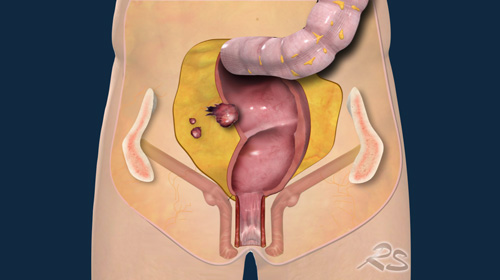

Peritoneal Carcinomatosis